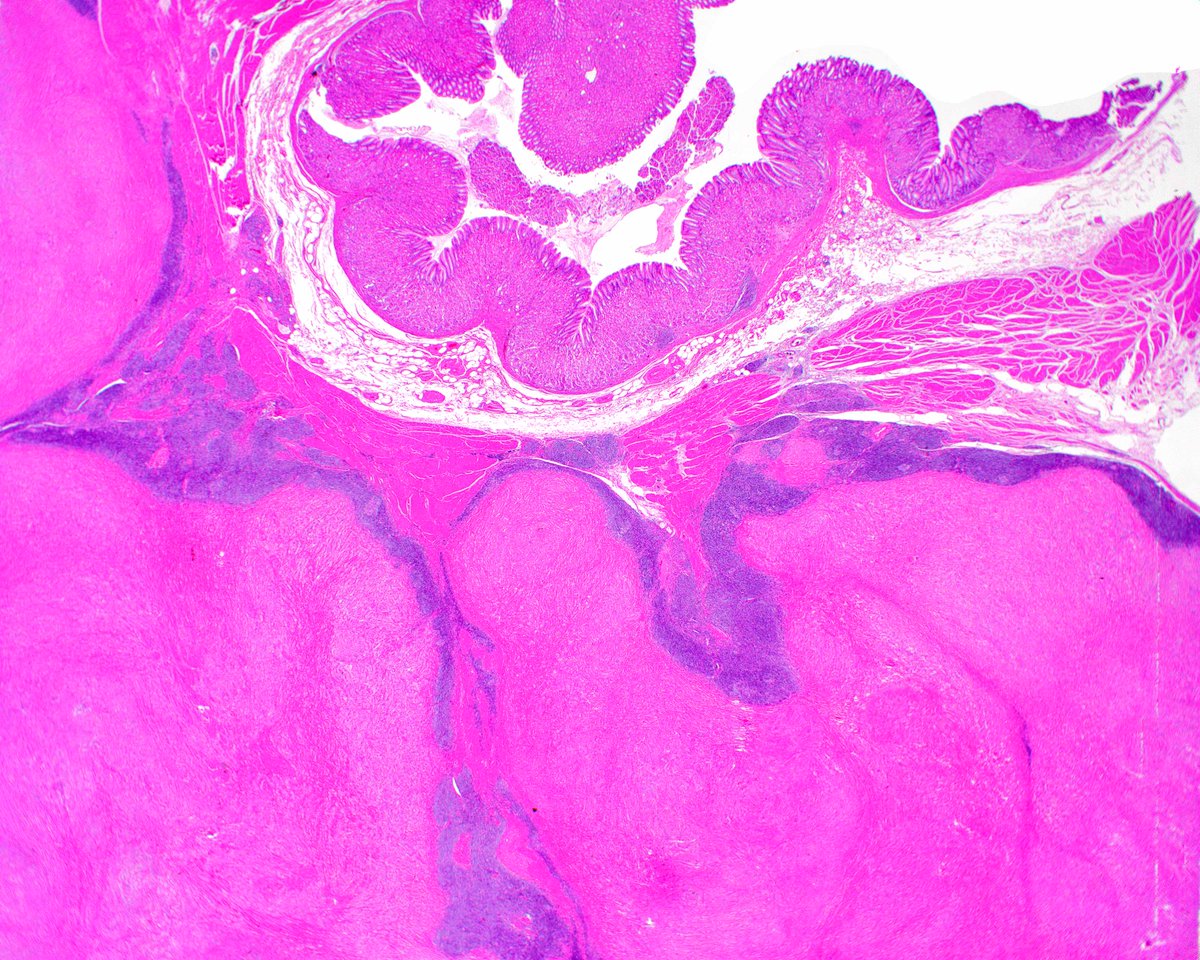

Stomach, hamarToma polyp. #Stomachpath